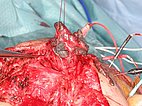

Intraoperative image of the site during resection of the occluded nidus (Prof. Reichart, Regensburg University Hospital). Step-by-step microsurgical preparation of the completely embolized nidus, which penetrates the entire cheek. To preserve the facial nerve, neuromonitoring of the facial branches is performed during the entire preparation, visible here from several needle electrodes at the right of the image.

Embolization of even small branches from the internal carotid artery is technically demanding and carries risk, as does complete occlusion of the nidus. Subsequent resection of the occluded nidus is equally difficult because the facial nerve is often directly embedded in the nidus. Intraoperative neuromonitoring to preserve the facial nerve is helpful here.